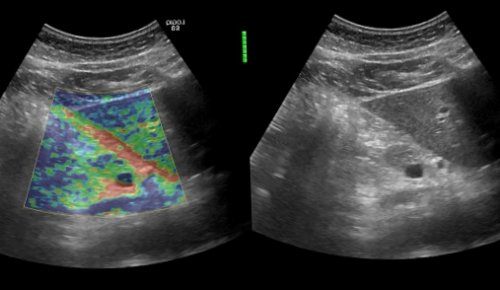

УЗИ с эластографией здоровой поджелудочной железы• эластаза кала – фермент поджелудочной железы, уровень которого при недостаточной ее работе, снижаетсяДиагностика панкреатита• падение массы тела, вплоть до истощения• есть изменения в копрограмме• копрологические исследования кала в норме (нет нейтрального жира, жирных кислот, мылов)Различают три степени тяжести хронического панкреатита: